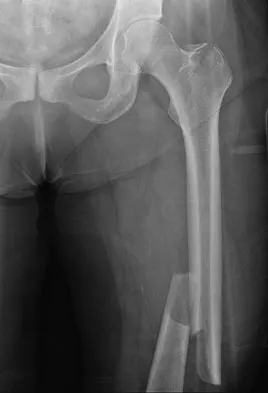

Question 16

Figure 22 shows the radiograph of a 7-year-old boy who underwent retrograde elastic nailing of a femoral shaft fracture. What is the most common problem following this procedure?